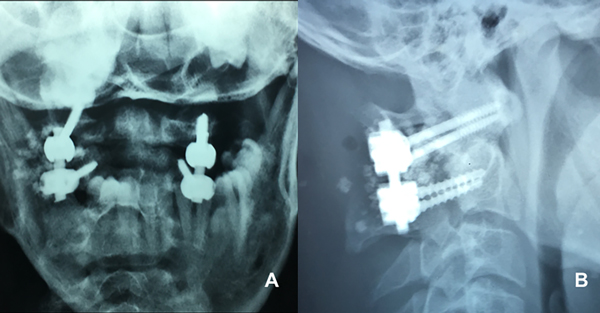

El retiro del halo-chaleco se lleva a cabo luego de realizar, en el postoperatorio inmediato, las radiografías de control que evidencian la correcta colocación del material protésico (Figura 8).

Figura 8. Rx frente (A.) y perfil (B.) postoperatorias.